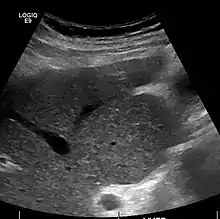

Ultrasound is routinely used in the evaluation of cirrhosis.[36] It may show a small and shrunken liver in advanced disease. On ultrasound, there is increased echogenicity with irregular appearing areas.[54] Other suggestive findings are an enlarged caudate lobe, widening of the fissures and enlargement of the spleen.[55] An enlarged spleen, which normally measures less than 11–12 cm in adults, may suggest underlying portal hypertension.[56] Ultrasound may also screen for hepatocellular carcinoma and portal hypertension.[36] This is done by assessing flow in the hepatic vein.[57] An increased portal vein pulsatility may be seen. However, this may be a sign of elevated right atrial pressure.[58] Portal vein pulsatility are usually measured by a pulsatility indices (PI).[57] A number above a certain values indicates cirrhosis (see table below).